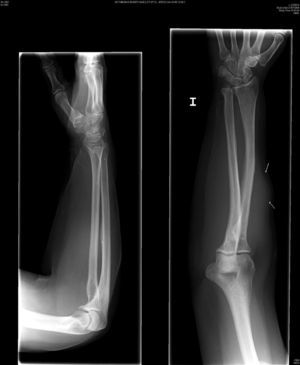

Mujer de 73 años con antedecente de melanoma coroideo en ojo derecho en 1999 tratado con braquiterapia. En mayo de 2008 acudió por nódulo en antebrazo izquierdo de 4 meses de evolución. A la exploración física se objetivaba un nódulo no doloroso a la palpación que parecía depender de la musculatura extensora. El hemograma, la bioquímica y el examen de orina fueron normales. La VSG de 26mm (0–20). La Rx del antebrazo (fig. 1) evidenció una masa densa en partes blandas sin erosión ósea. La ecografía (fig. 2) objetivó una tumoración ovalada, sólida con flujo arterial en su interior. La RM (fig. 3) mostró una masa sólida hiperintensa en T1, levemente hiperintensa en T2 y algo más brillante en STIR.